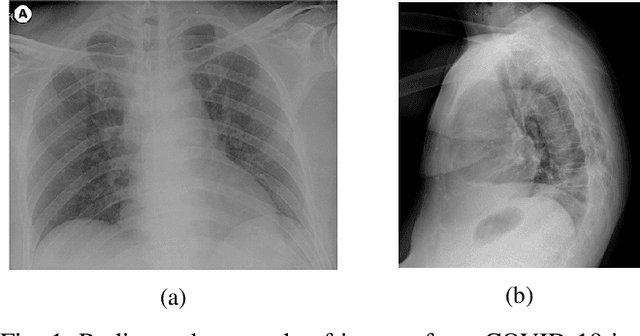

Confronting the pandemic of COVID-19 caused by the new coronavirus, the SARS-CoV-2, is nowadays one of the most prominent challenges of the human species. A key factor in slowing down the virus propagation is the rapid diagnosis and isolation of infected patients. Nevertheless, the standard method for COVID-19 identification, the Reverse transcription polymerase chain reaction (RT-PCR) method, is time-consuming and in short supply due to the pandemic. Researchers around the world have been looking for alternative screening methods. In this context, deep learning applied to chest X-rays of patients has been showing promising results in the identification of COVID-19. Despite their success, the computational cost of these methods remains high, which imposes difficulties in their accessibility and availability. Thus, in this work, we propose to explore and extend the EfficientNet family of models using chest X-rays images to perform COVID-19 detection. As a result, we can produce a high-quality model with an overall accuracy of 93.9%, COVID-19, sensitivity of 96.8% and positive prediction of 100% while having about 30 times fewer parameters than the baseline literature model, 28 and 5 times fewer parameters than the popular VGG16 and ResNet50 architectures, respectively. We believe the reported figures represent state-of-the-art results, both in terms of efficiency and effectiveness, for the COVIDx database, a database comprised of 13,800 X-ray images, 183 of which are from patients affected by COVID-19.